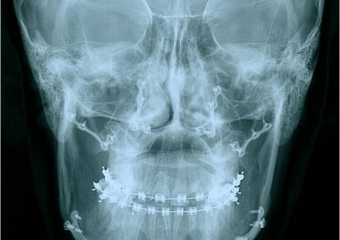

Telerradiografia frontal após a cirurgia - Clínica Cliniface

Telerradiografia frontal após a cirurgia